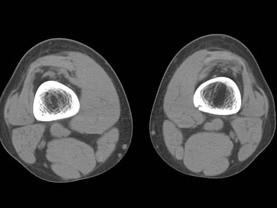

问题 病例,女,15岁,因感右股骨下段不适,不痛不胀,体查无特殊,请结合所提供的图像,选择最佳选项是 ( )

选项 A、良性骨肿瘤 B、骨结核 C、非骨化性骨纤维瘤 D、骨囊肿 E、纤维性骨皮质缺损

答案 E